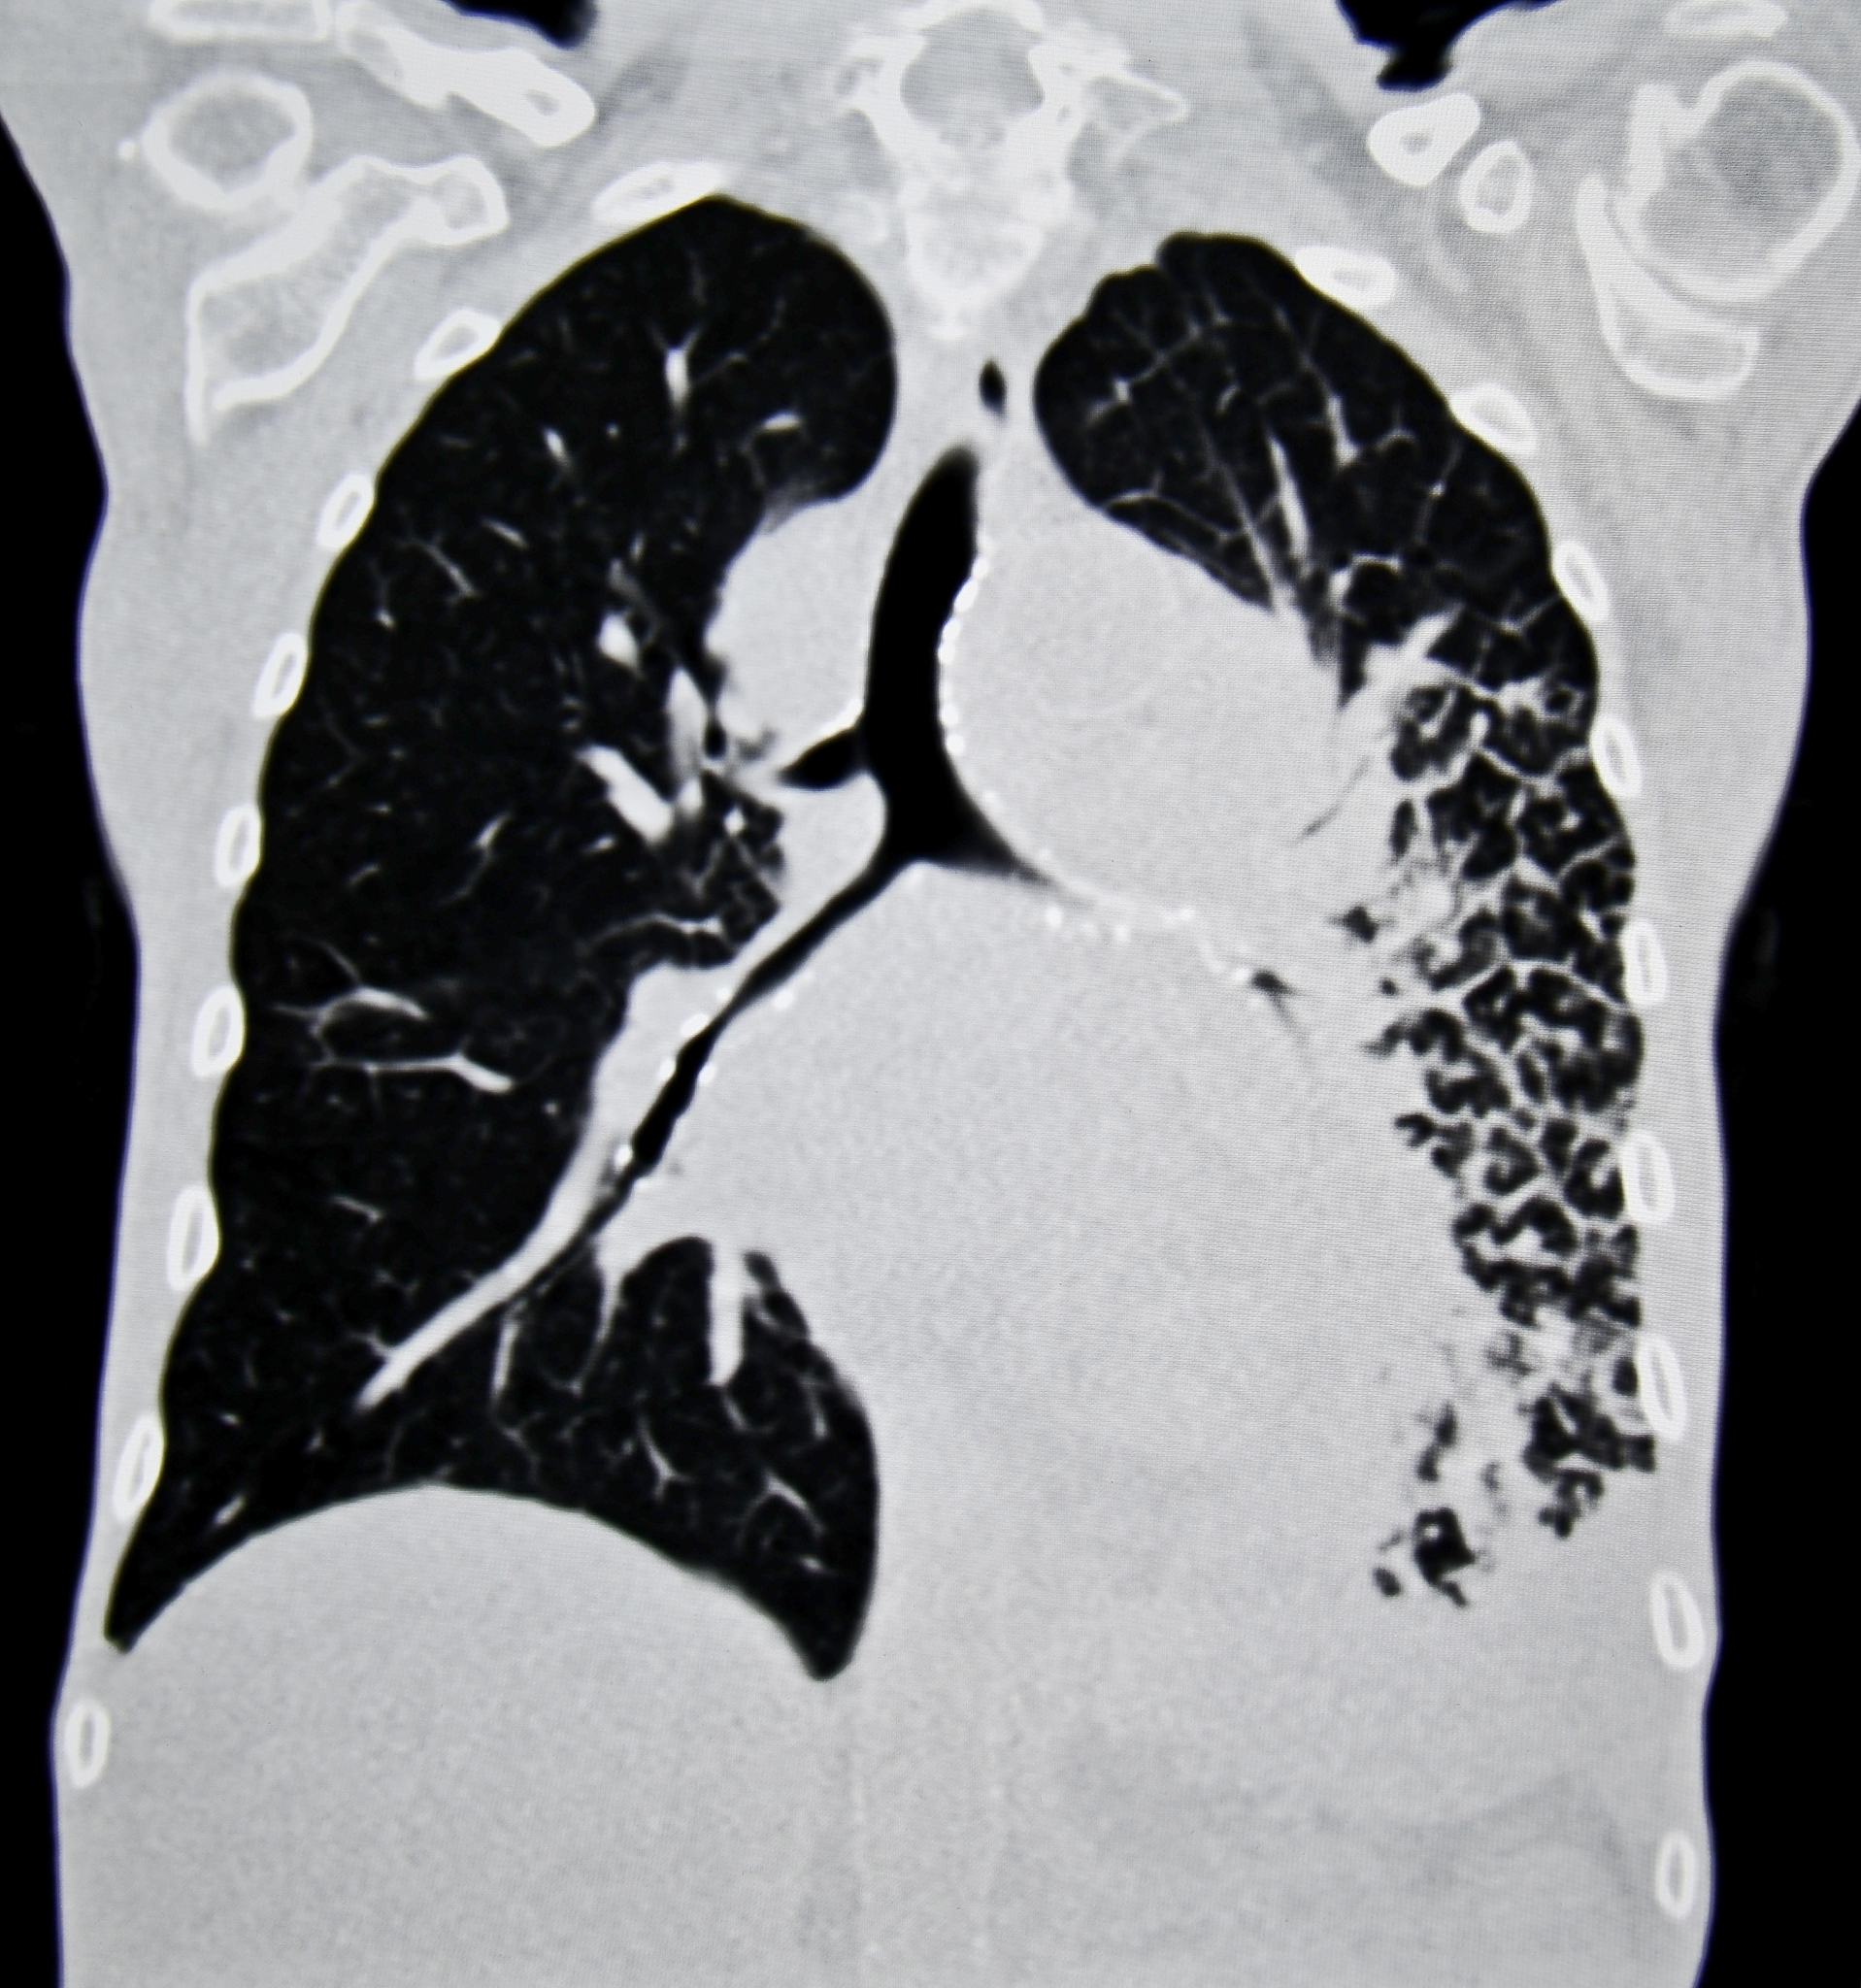

根据您描述的结果,您的左肺上叶尖后段存在结节,并且经过评估被分类为Lung-RADS 4A类。这意味着该结节可能为恶性,但需要进一步评估以确定其性质。建议您在3个月后进行双肺多发微小结节的复查,同时注意保持肺部健康,避免吸烟和有害气体的暴露。双肺存在慢性炎症,需要密切关注任何症状变化,及时就医并进行治疗。

左肺上叶尖后段结节Lung-RADS 4A类建议3个月复查双肺多发微小结节双肺慢性炎症。